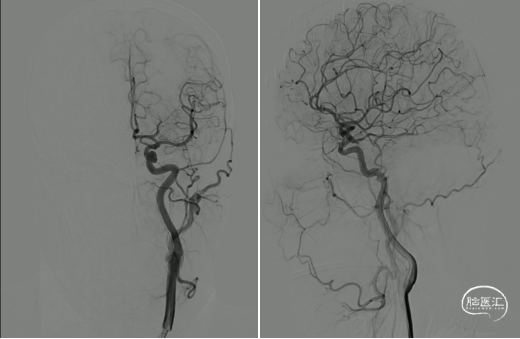

患者平卧位,双管喉罩全麻,术野常规消毒铺无菌巾,以Seldinger氏技术穿刺右股动脉置8F鞘,肝素盐水(5000U/500ML)持续滴注,导丝引导下送入5F脑造影导管依次行双侧颈总动脉、双侧椎动脉血管造影,超选择性左侧颈内动脉3D造影。

造影所见:双侧颈动脉血管稍迂曲僵硬,双侧后交通动脉开放,左侧颈内动脉后交通段可见一“囊状”突起,大小约6.19mm*4.07mm*2.35mm,瘤颈4.03mm,基底宽,边缘不光整,有两个子瘤,指向后下方,后交通动脉从瘤颈处发出。

造影